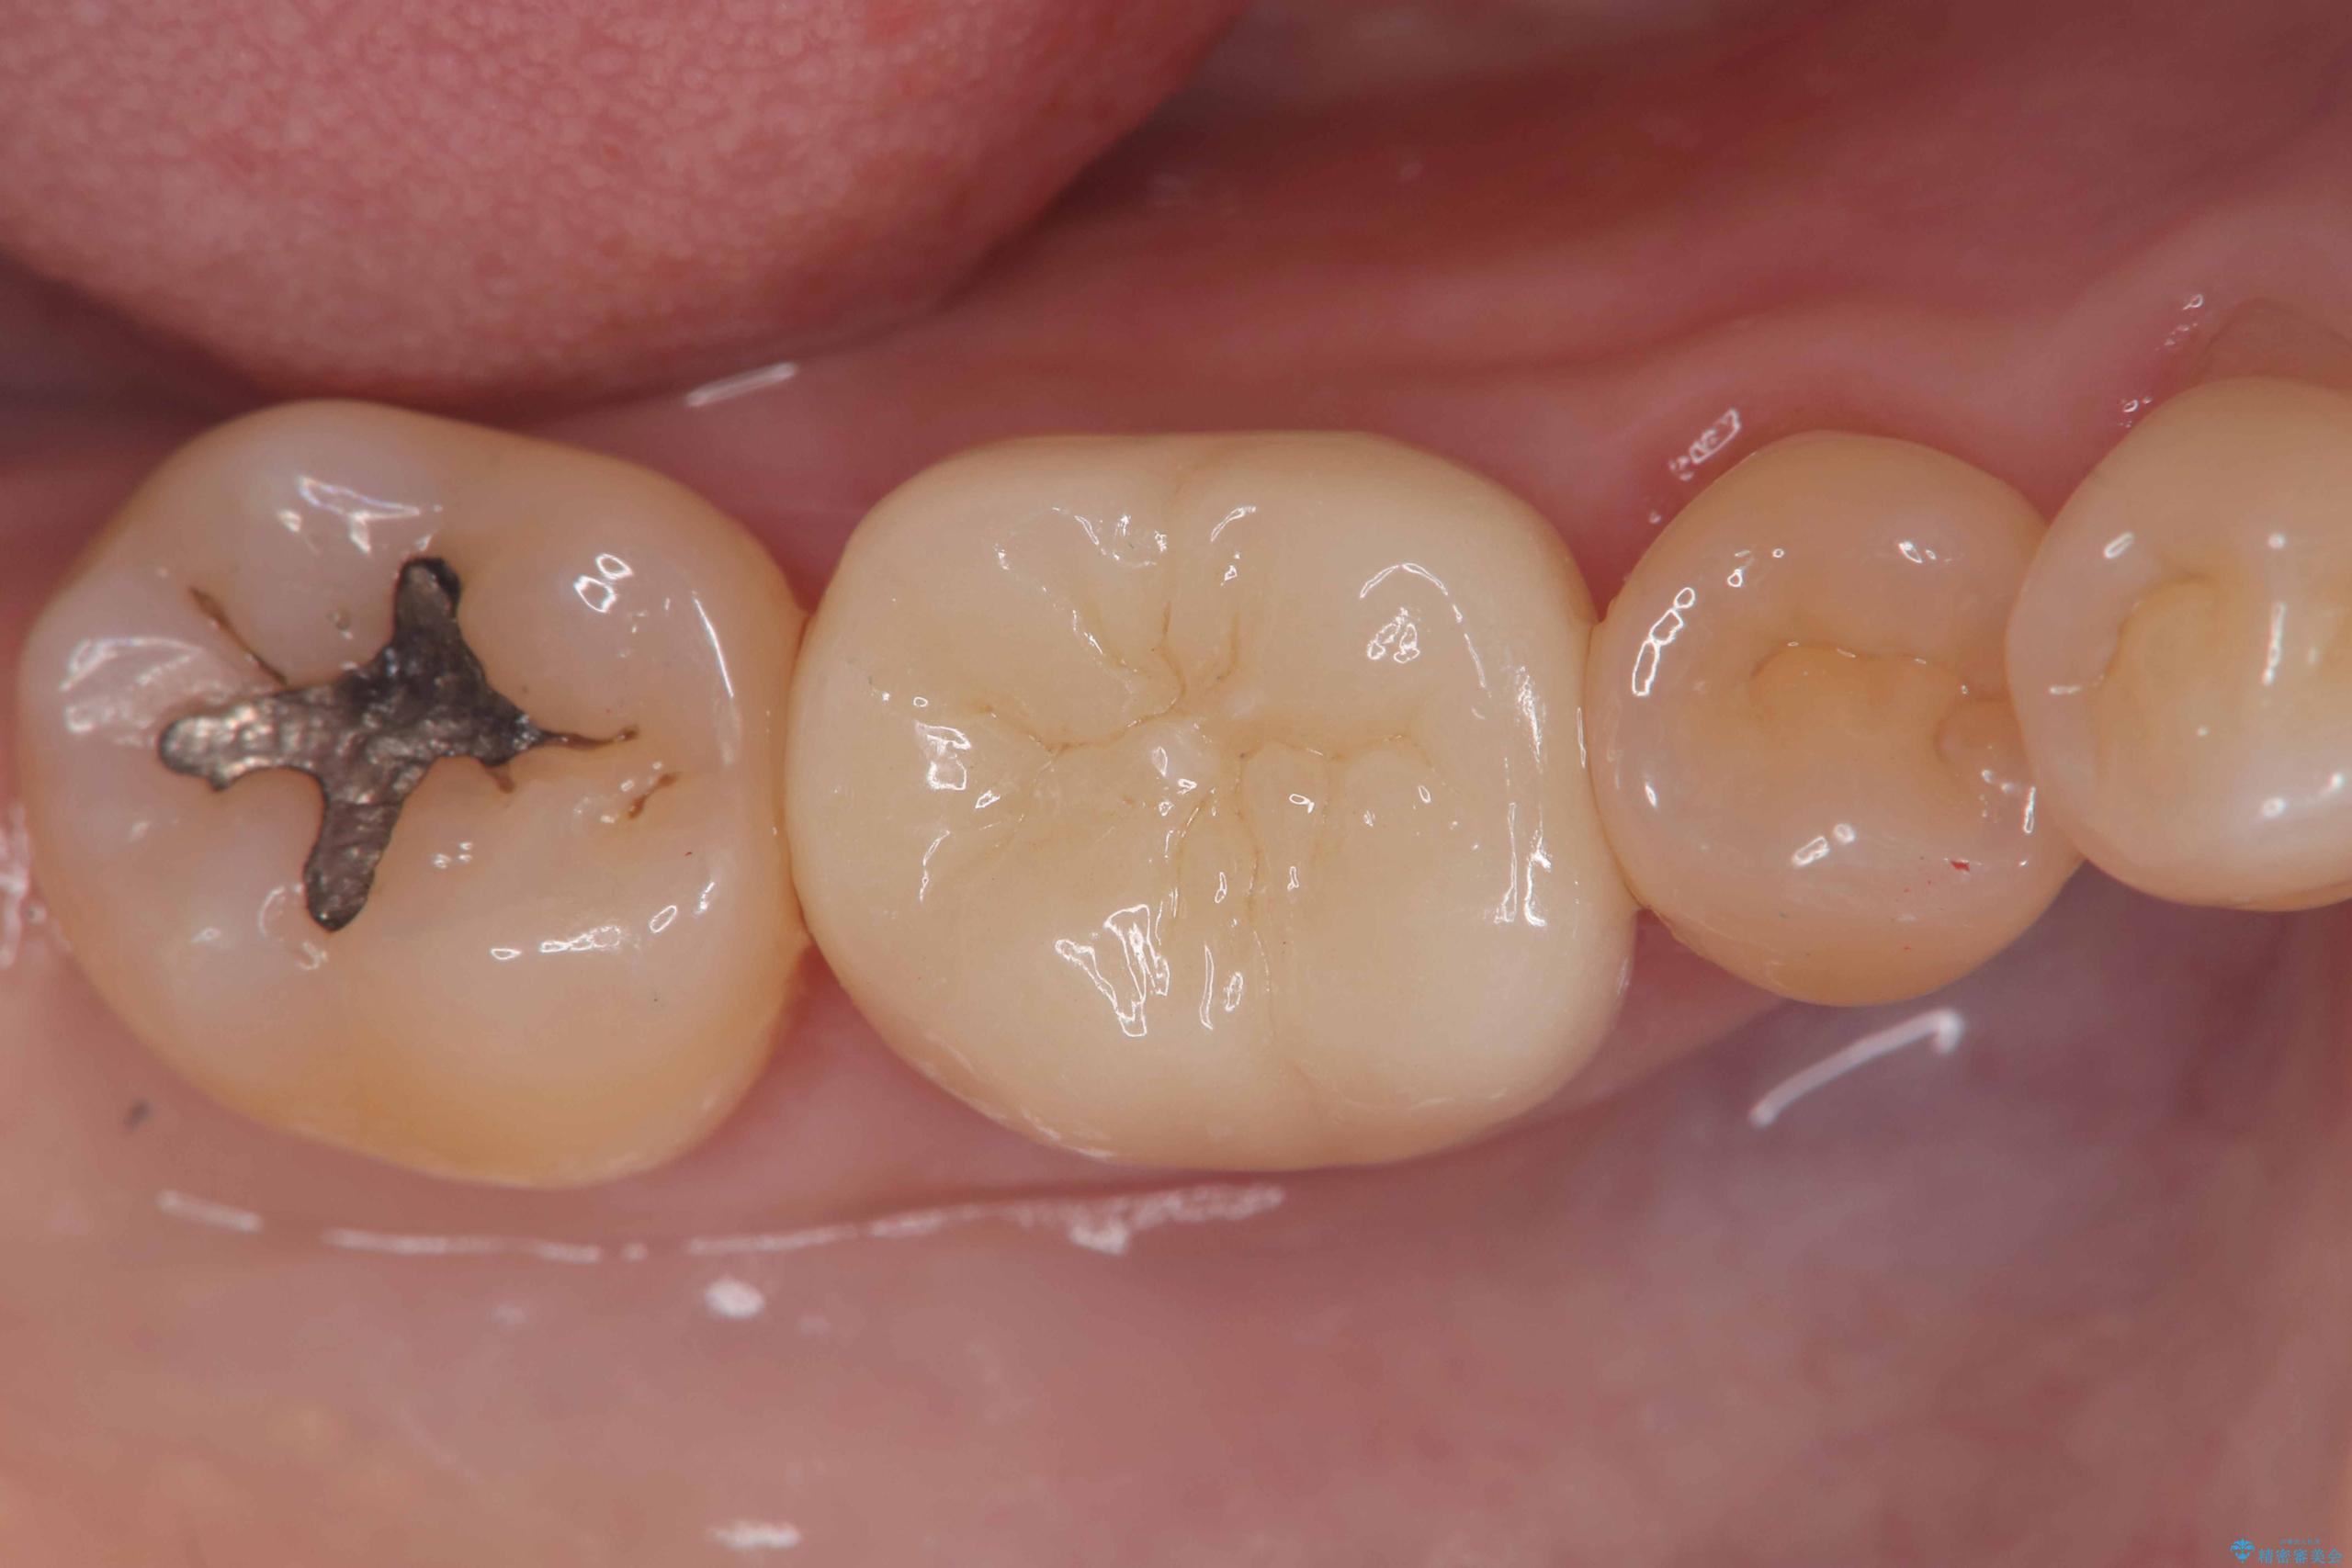

- 「銀歯を白くしたい」を主訴に来院された患者様です。銀歯を外し虫歯を除去後、オールセラミッククラウンで治療を行いました。

銀歯を外して内部の虫歯を丁寧に除去した後、オールセラミッククラウンにて修復を行いました。審美性と機能性の両面で改善が得られ、患者様にもご満足いただきました。